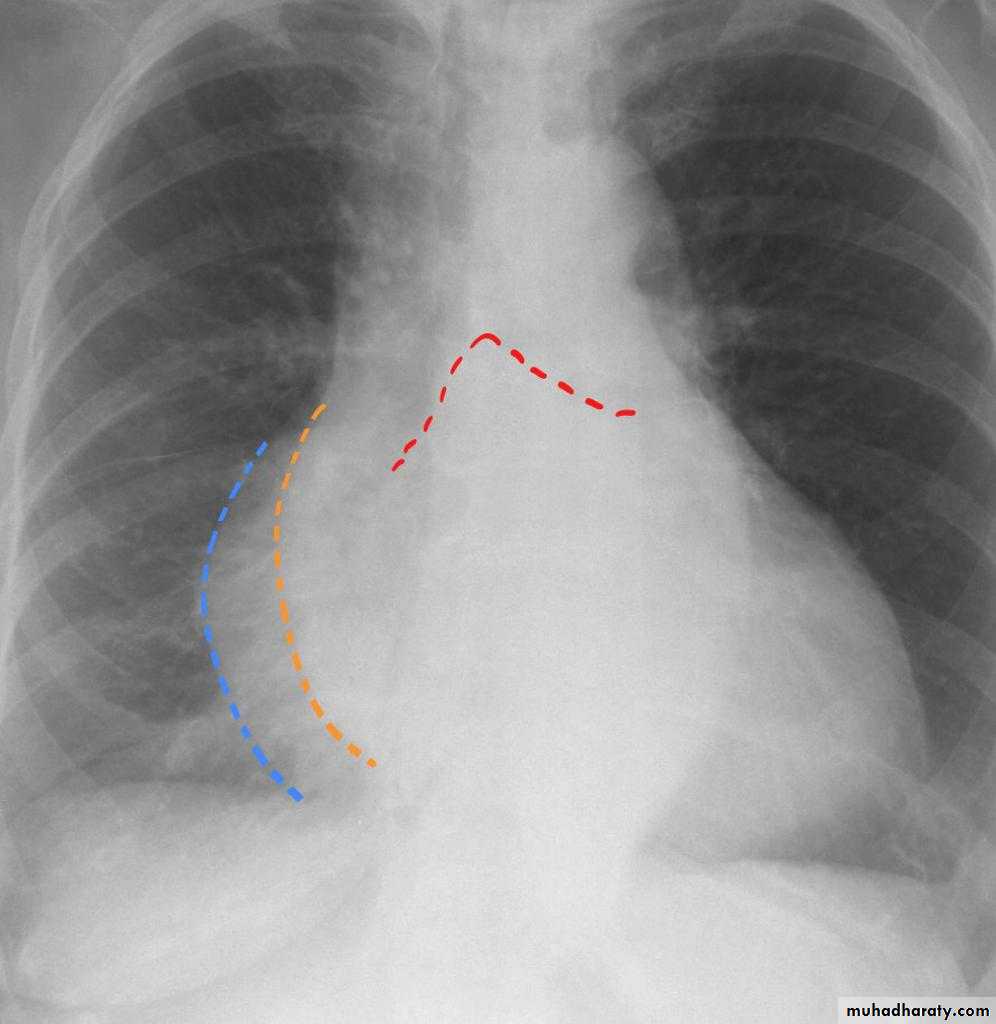

Pericardial effusion Globe shape CXR of adult, PA view shows:Globular enlargement of the heartgiving a water bottle configuration (globe heart, pumpkin shape heart)